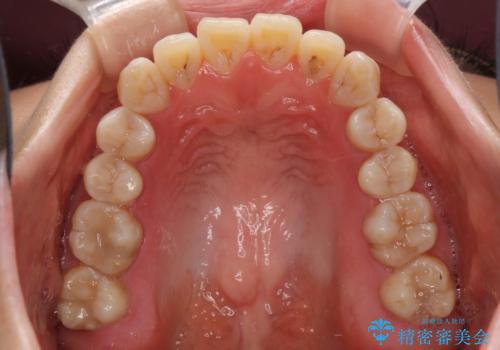

話しにくいオープンバイト インビザラインによる矯正治療

- 前歯の上下スペースによる話しにくさを気にして来院された患者様です。

インビザラインにより上下の前歯の隙間を閉じていくこととしました。

上下の奥歯を圧下させるようにすることで、前歯を接触させるように計画しました。

隙間に舌が入り込むことが話しにくさに繋がっていたため、舌の筋肉のトレーニングも並行して行い、話しにくさの改善と後戻りの抑制を図りました。